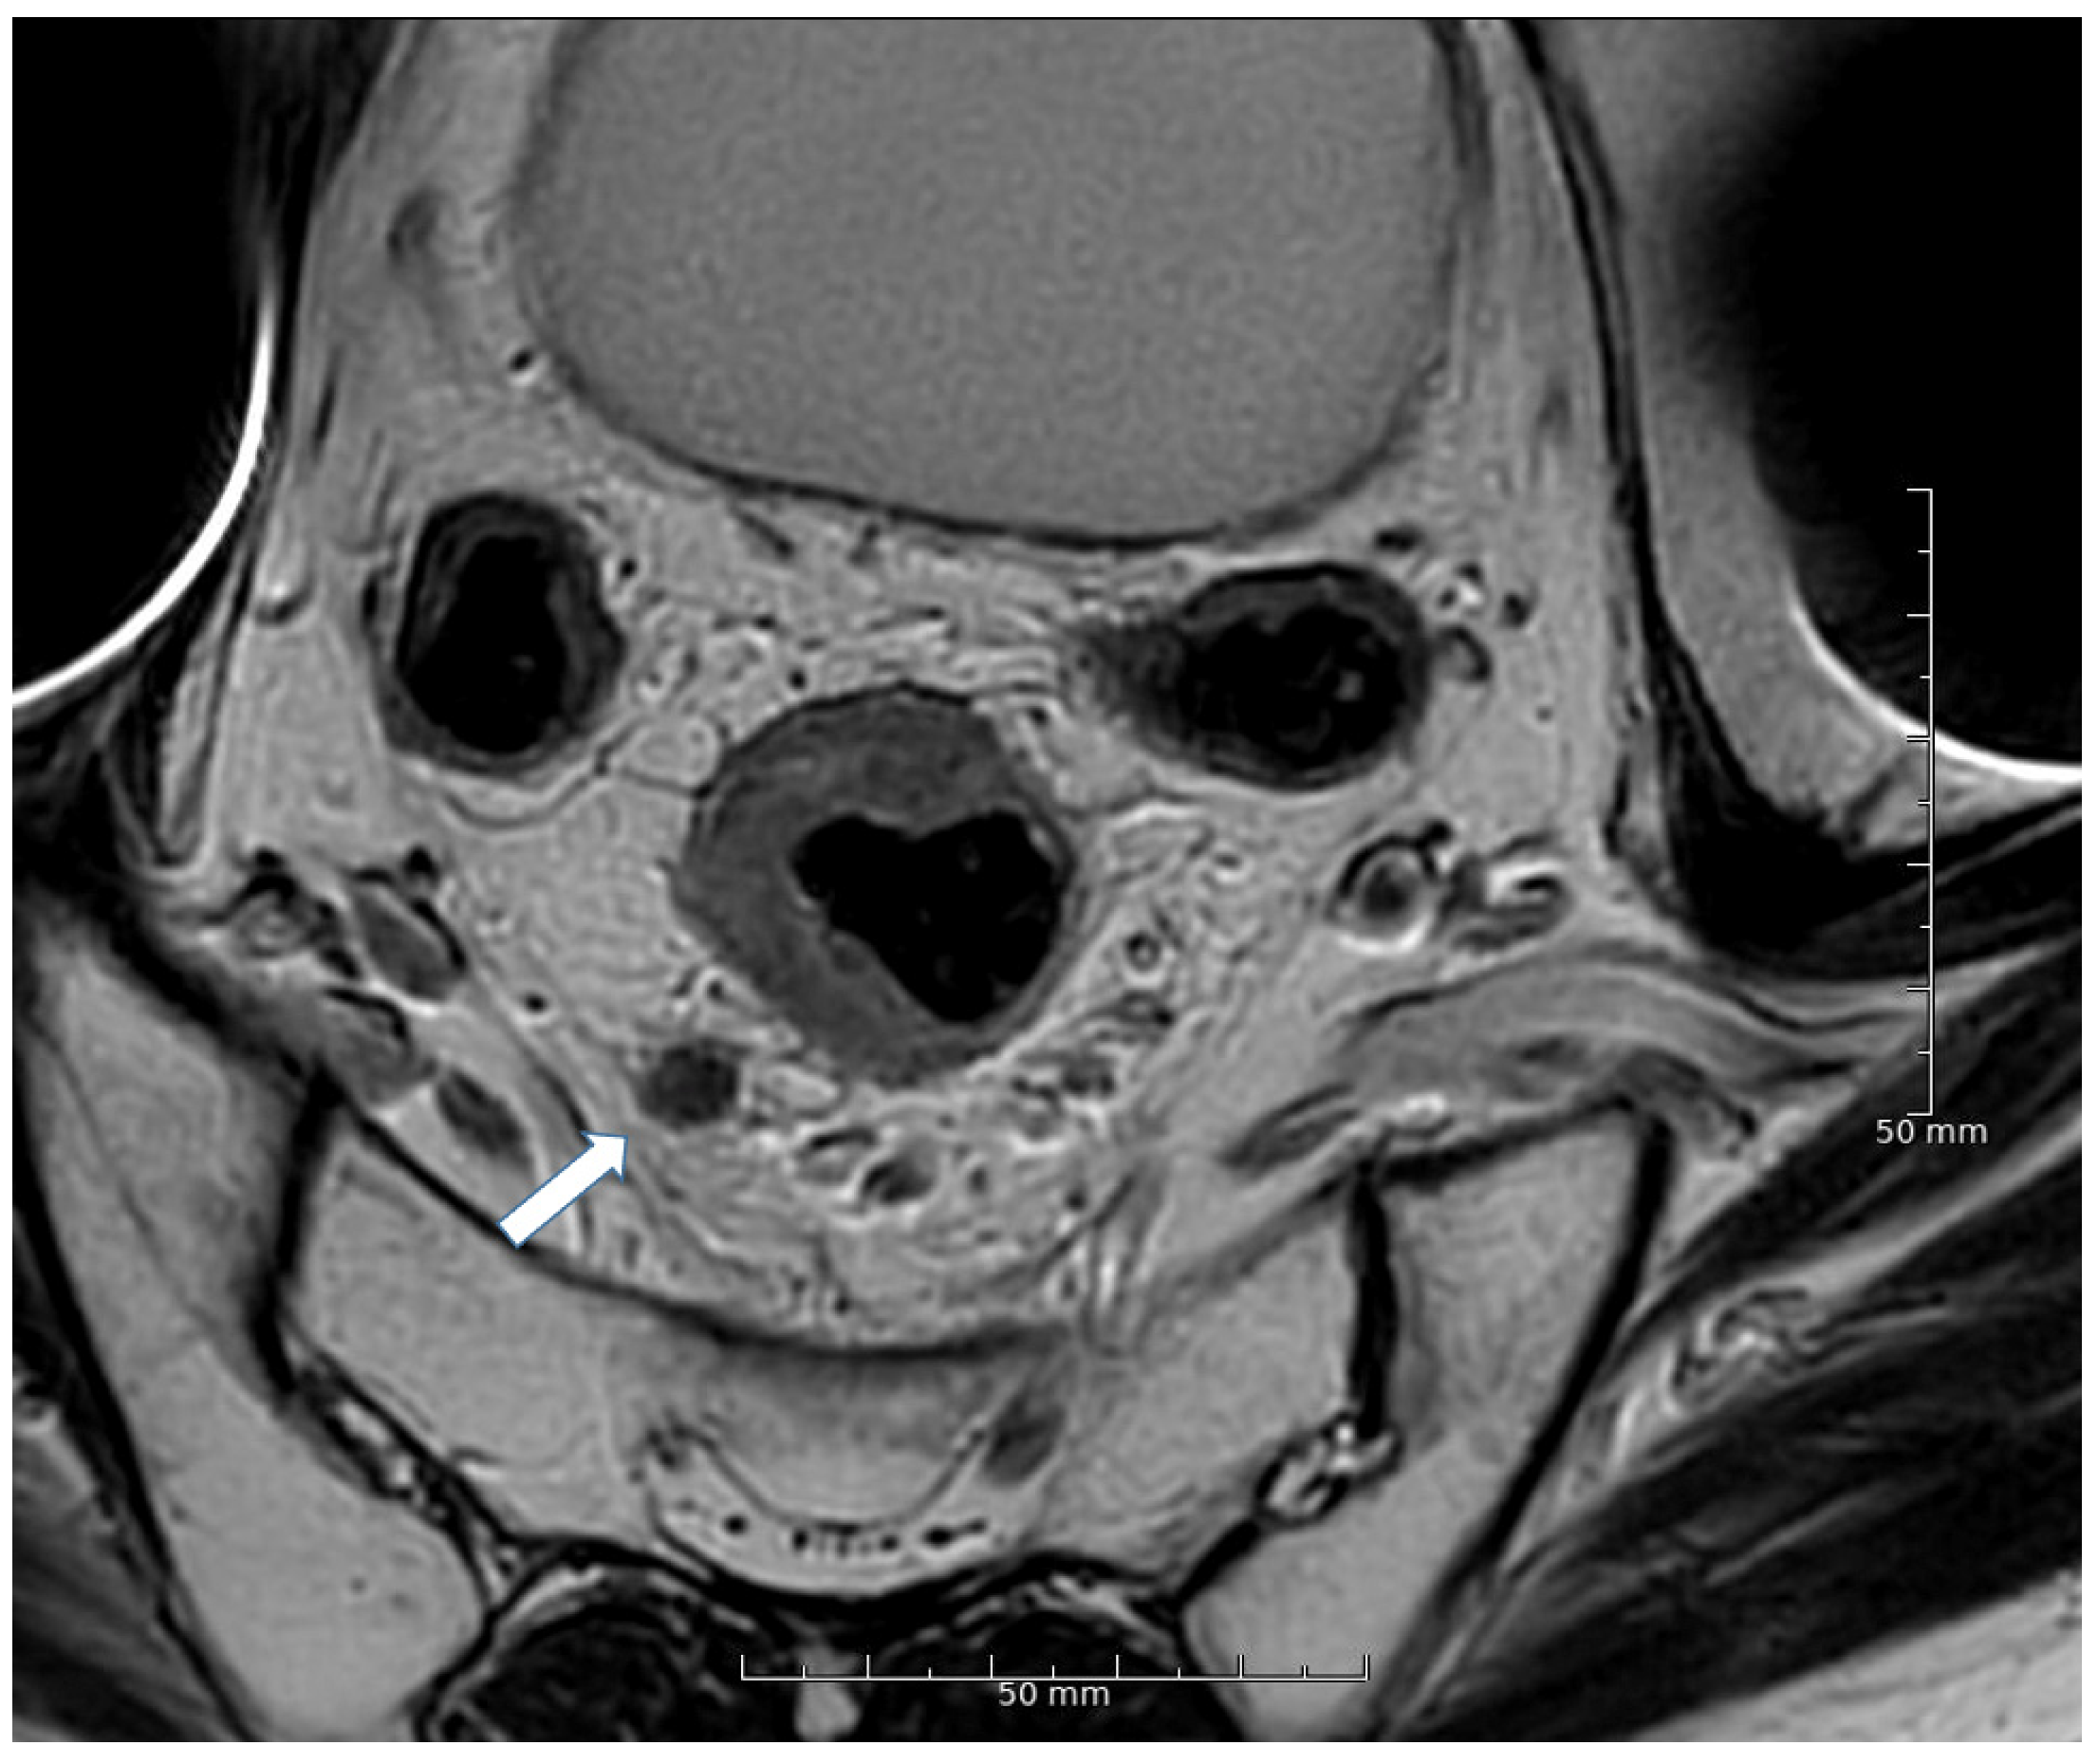

2.3. Lymph Node Assessment